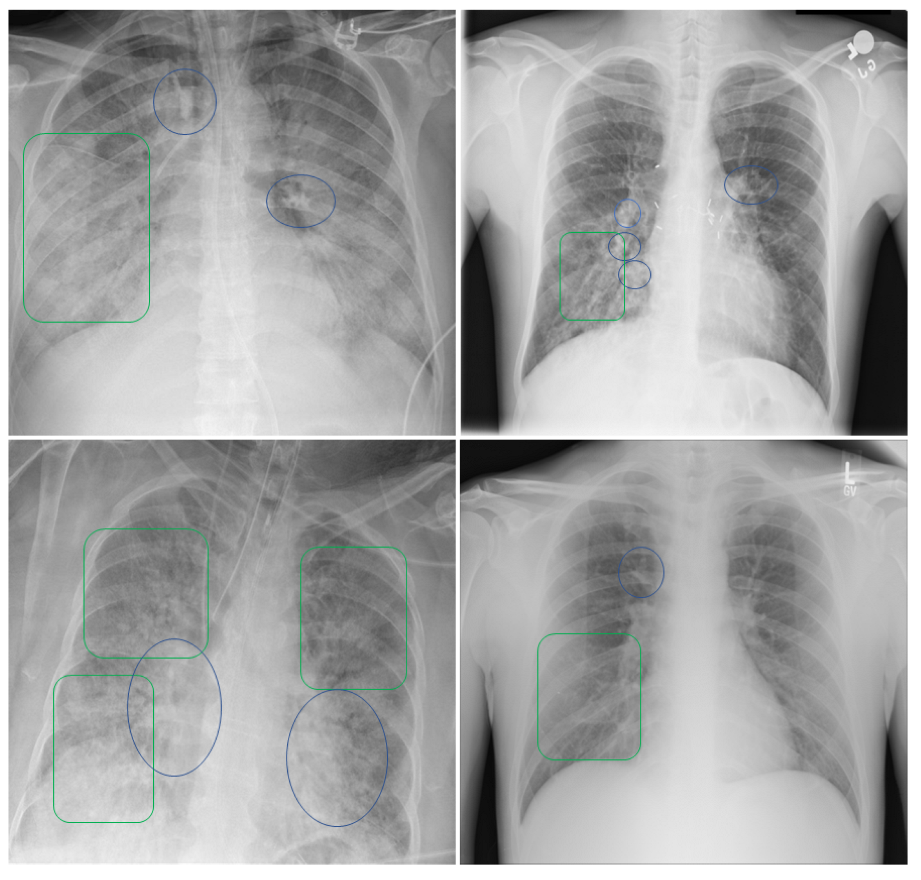

Figure 14 shows an example of typical chest X-ray images used for diagnosis. It can be observed that there are ground-glass opacities in the lungs of certain patients, which are identified using green rectangles. Pulmonary lobes and patchy consolidations are identified using blue ovals, indicating the presence of fibrosis or nodules. Doctors often use these features to determine whether patients are in a state of pneumonia, as well as its severity. Our model is designed to learn these features in order to achieve correct classification.

Figure 14. Analysis and diagnosis using patient CXR images.